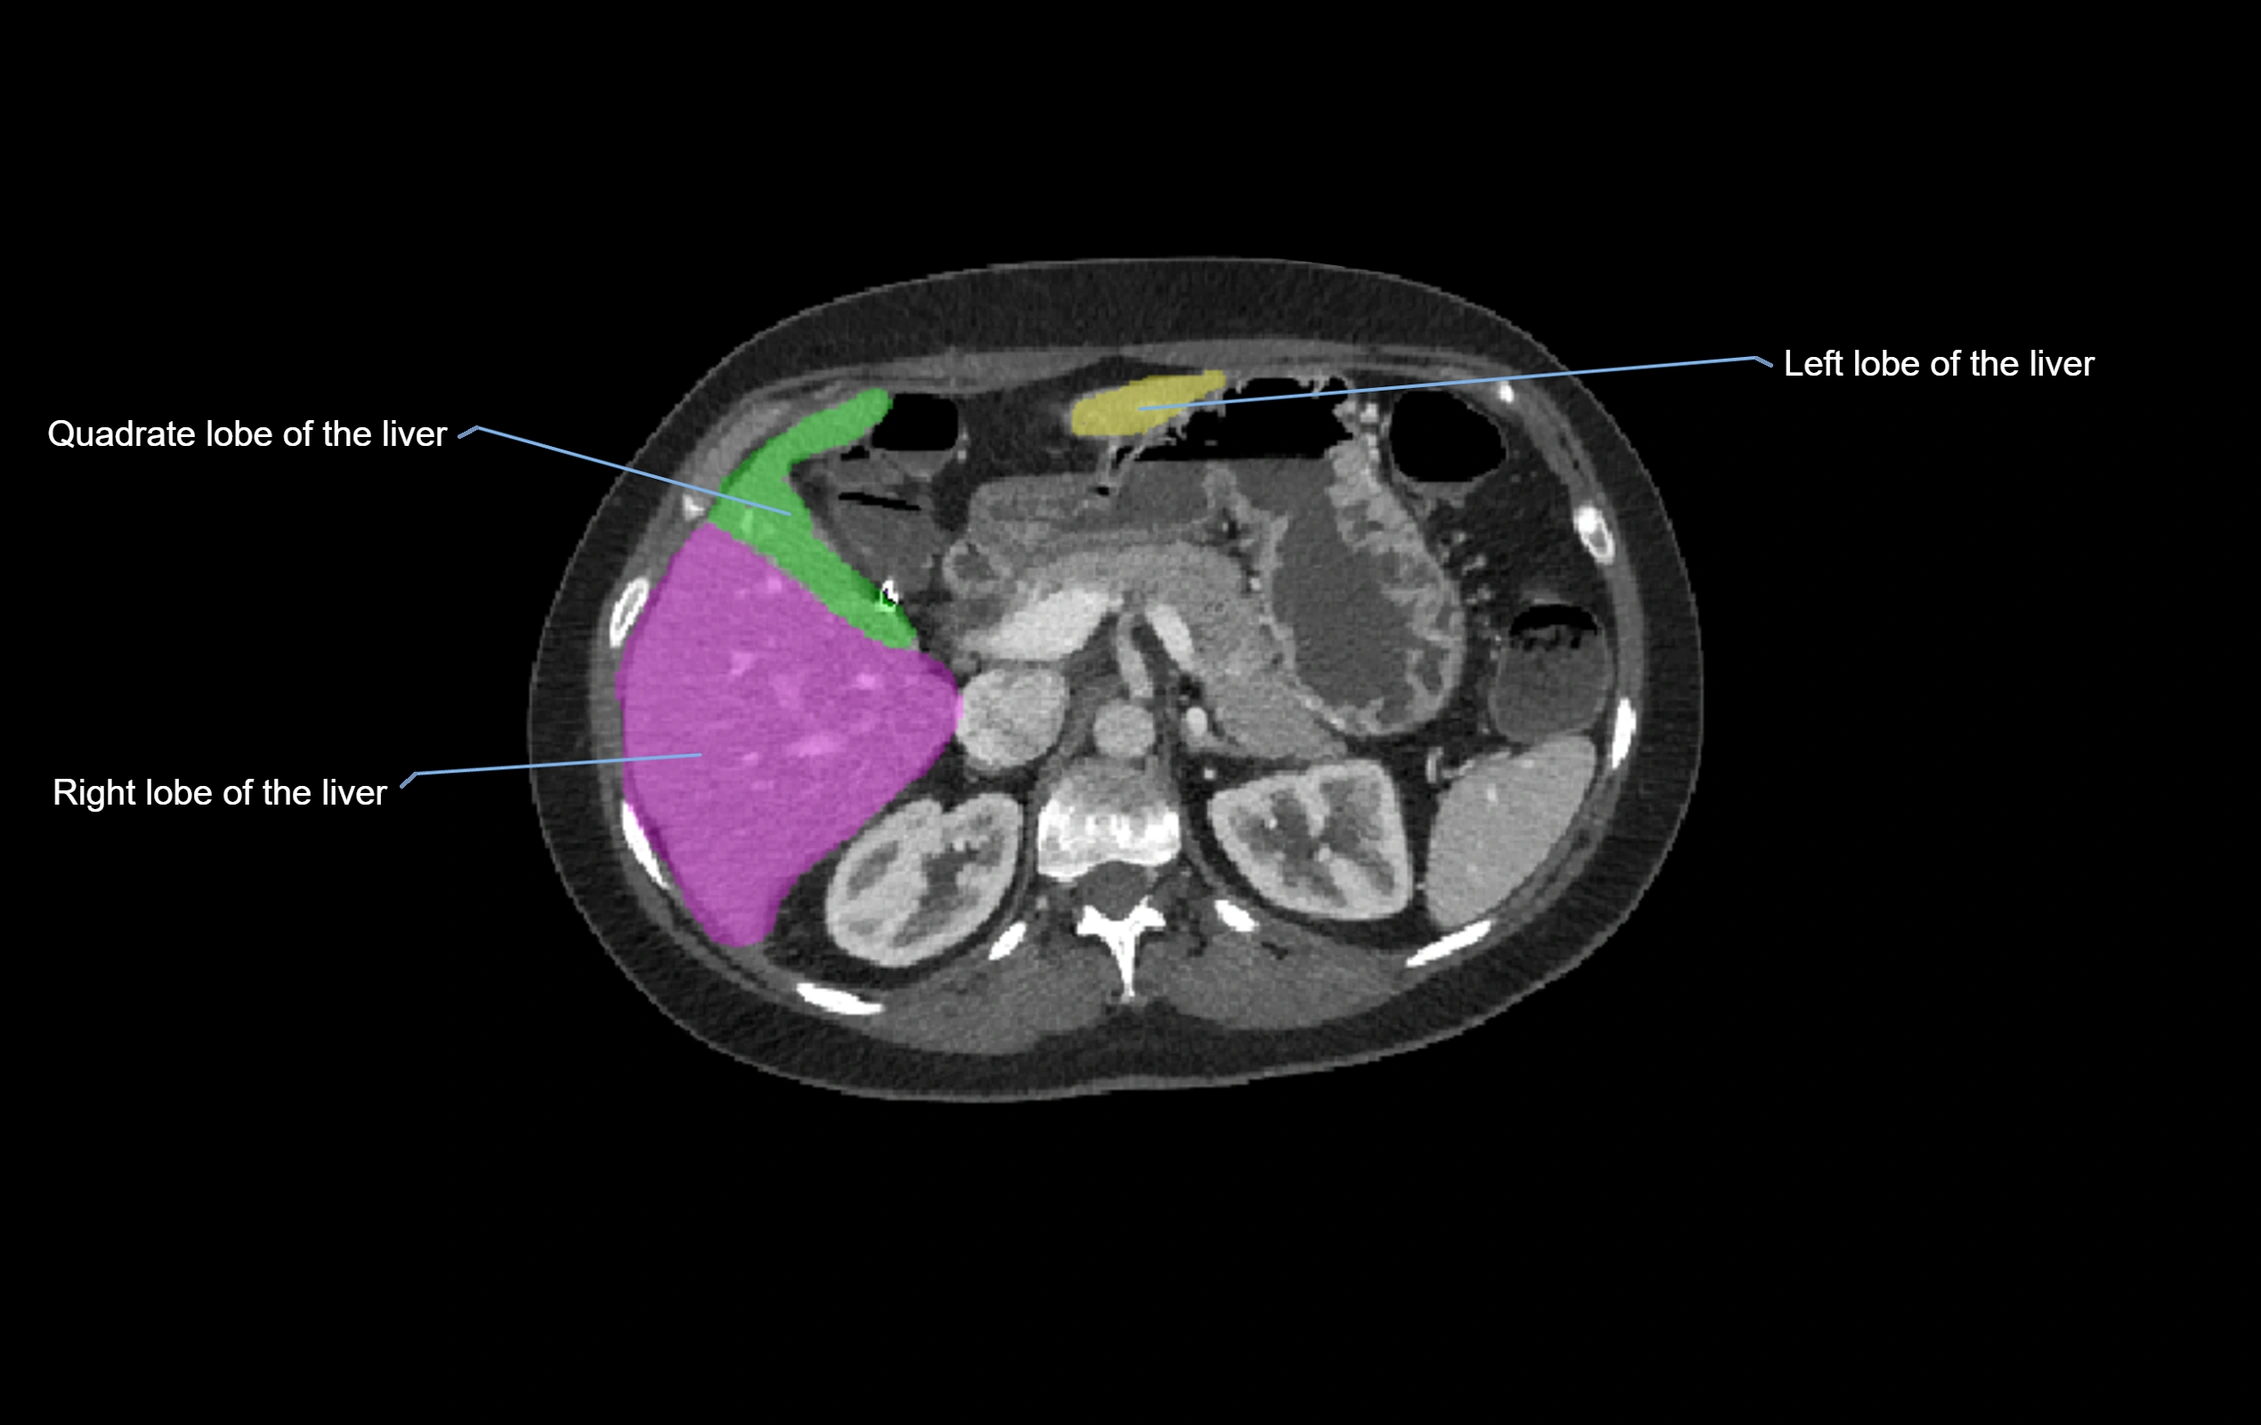

CT Image

image